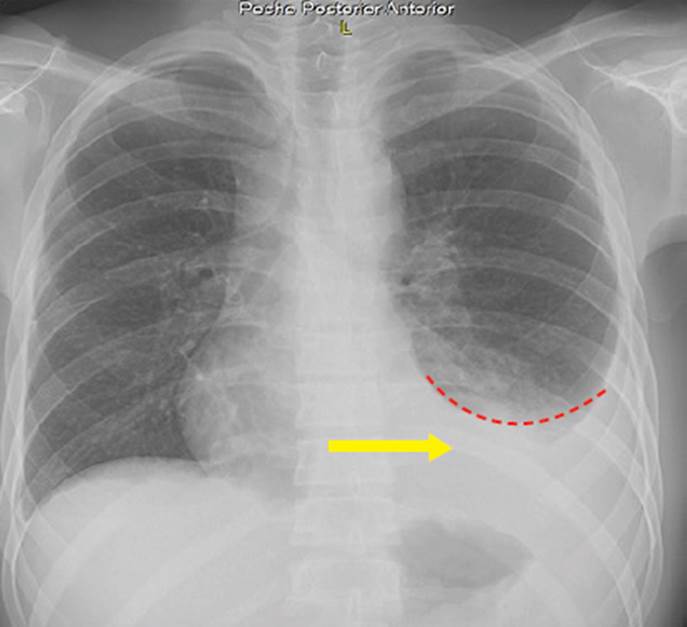

En la Tabla 1 se muestran los exámenes de laboratorio que se realizaron durante la hospitalización del paciente: baciloscopia en esputo con resultado negativo, baciloscopia en orina con resultado 5 BAAR y baciloscopia en heces que resultó positiva (+), ecografía torácica con reporte de líquido libre en ambos hemitórax, un volumen de 400 ml en el hemitórax izquierdo y 150 ml en el derecho; radiografía de tórax que muestra derrame pleural bilateral con predominio izquierdo (Figura 1); ecografía abdominal con hallazgos de esplenomegalia y nódulos hipoecogénicos (Figura 2); test de adenosina deaminasa en líquido pleural con valor 33. Los resultados de carga viral para VIH fueron 181 000 copias/ml y CD4: 63.

Figura 1 La radiografía de tórax anteroposterior muestra radiopacidad homogénea en tercio inferior del campo pulmonar izquierdo (flecha amarilla), que obtura seno costofrénico, con signo de menisco (líneas punteadas rojas). Seno costofrénico derecho libre y elementos óseos y partes blandas con características habituales